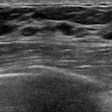

Using AI with mammography can help select women for breast MRI